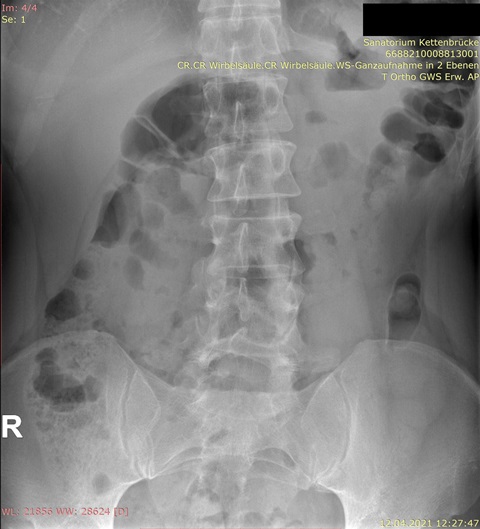

Habe die Bilder. Für mich als Laie sieht es nicht so schlimm aus auf den Röntgenaufnahmen, aber ich bin in der Realität total asymmetrisch und schief, und am extremsten ist, dass die Rippen/Brustkorb auf der rechten Seite viel mehr rausstehen und das optisch sehr auffällt.

Im Anhang die Bilder.

Ich (auch Laie) sehe nur eine geringe Seitabweichung der Wirbelsäule, aber eine deutliche Rotation, erkennbar an den "Kringeln" der Dornfortsätze und Querfortsätze. Ich denke auch, dass da ein Spezialist gefragt ist.rudi777 hat geschrieben: ↑Do, 22.04.2021 - 16:20 Für mich als Laie sieht es nicht so schlimm aus auf den Röntgenaufnahmen, aber ich bin in der Realität total asymmetrisch und schief, und am extremsten ist, dass die Rippen/Brustkorb auf der rechten Seite viel mehr rausstehen und das optisch sehr auffällt.